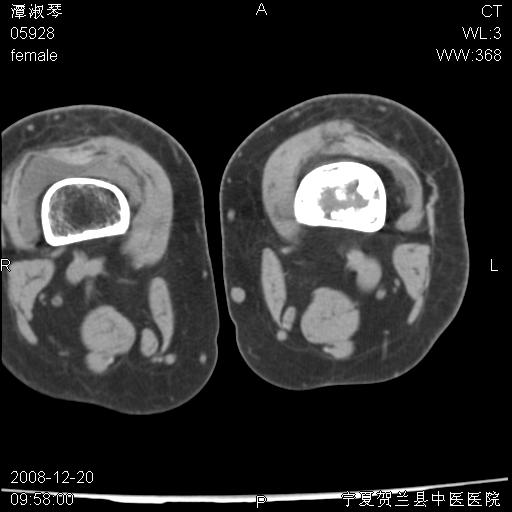

标题: CT17526:请各位看看是啥? [打印本页]

标题: CT17526:请各位看看是啥?

内生软骨瘤?骨梗死?

考虑内生软骨瘤可能性大

考虑-----骨梗死+退变

支持骨梗死,退行性骨关节病,膝关节积液.

考虑骨梗死可能性大

支持骨纤或内生软骨瘤或骨梗死,退行性骨关节病,膝关节积液.

骨梗死可能性大

左股骨下段骨梗死。双膝退变。

支持:内生软骨瘤或骨梗死!另:退行性骨关节病,膝关节积液。

左胫骨下端松质骨及髓腔内可见点片状高密度灶,骨皮质无明显膨胀及变薄。病变范围较长。支持骨梗死,退行性骨关节病,膝关节积液